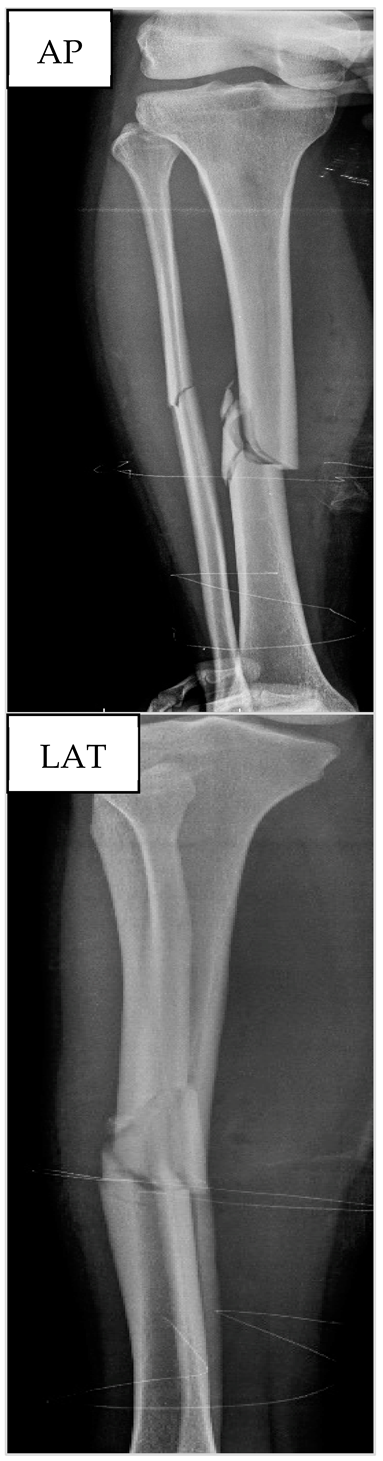

3.2. Patient nº2